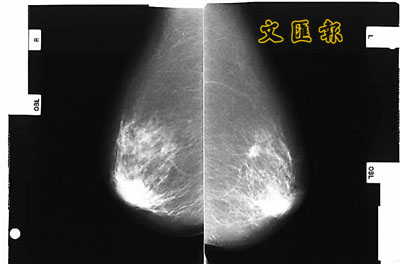

X光片下的乳癌組織(左、右)。